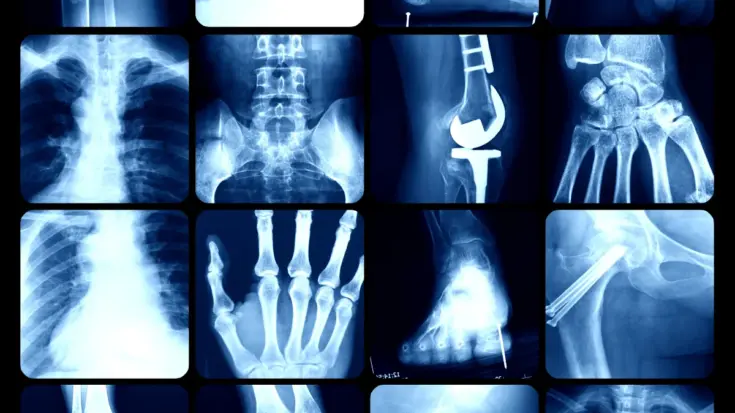

The advantages and disadvantages of X-ray detectors include multiple purposes, such as non-invasive imaging, to be effective in detecting bone structure, while the disadvantages include radiation exposure to anticipate, limited details on complex fractures, and limited soft tissue detection.

The advantages of X-ray detectors can be used for various purposes, such as non-invasive imaging, to be effective in detecting bone structure, while the disadvantages include radiation exposure to anticipate, limited details on complex fractures, and limited soft tissue detection. Here are the advantages and disadvantages of X-ray detector:

In the medical world, X-ray detectors are very effective in detecting bone structure. This device is able to detect and capture detailed images when a patient has a fracture dislocation and other bone abnormalities.

Not being able to detect details on complex fractures is another drawback of this device. Its limitation in providing enough detail makes it impossible for doctors to make a proper evaluation.

Another drawback of X-rays is the limited soft tissue detection. When compared to other imaging modalities such as MRI or ultrasound, X-ray is less effective in distinguishing soft tissues such as muscles, tendons, and internal organs.